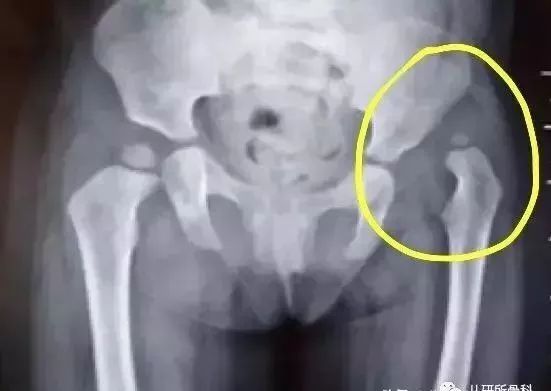

由于骨化中心是真正的骨组织,在X线片上可以显影,所以,6个月以上照X线片,结果会更准确。下图显示的是髋关节的X线片,圈内标记的就是脱位的髋关节。一旦发现这种情况,就需要进行专业的治疗了。